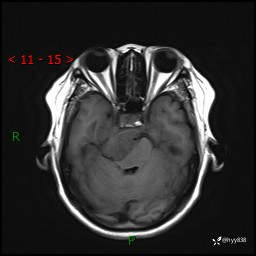

颅脑MRI平扫+增强